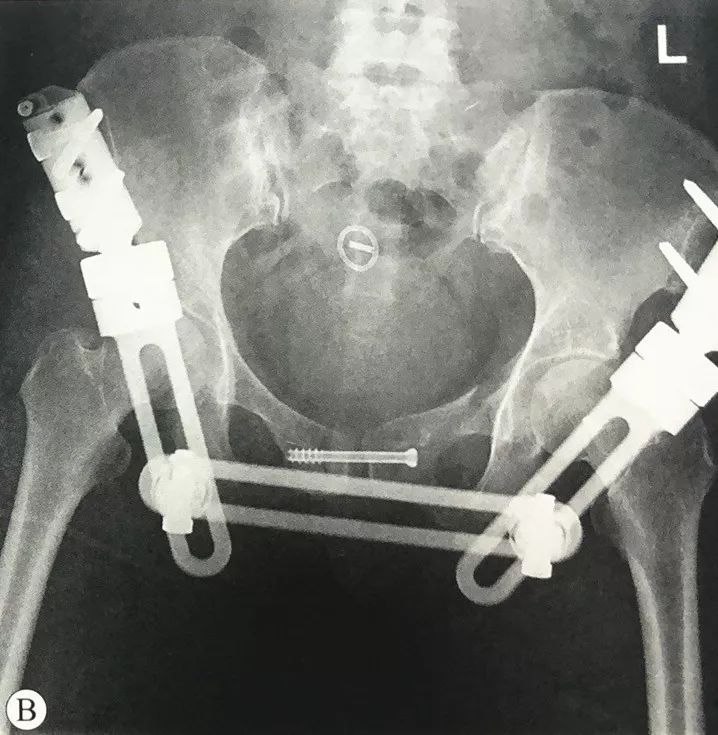

骨科微创时代 骨盆骨折不再是 大 问题 患者

早读 骨盆骨折的闭合复位经皮微创技术 医贰叁云学院 微信公众号文章阅读 Wemp

骨盆环骨折的治疗策略